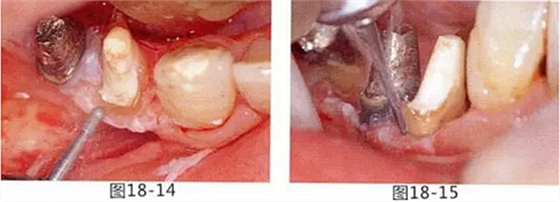

病例10

有少數(shù)牙體殘存的病例,需要進(jìn)行修復(fù)處理,將基牙和鉤牙部位的牙周袋去除以及對(duì)頰舌側(cè)進(jìn)行FGG(游離齦移植)來獲取附著齦的病例

圖19-1 右下3,4,左下3,4,5殘存牙頰側(cè)面照。唇頰側(cè)沒有附著齦。

圖19-2 同部位的舌側(cè)面照。雖然有1mm左右角化牙齦,但是進(jìn)行預(yù)測(cè)切開的話,會(huì)使角化牙齦完全消失。